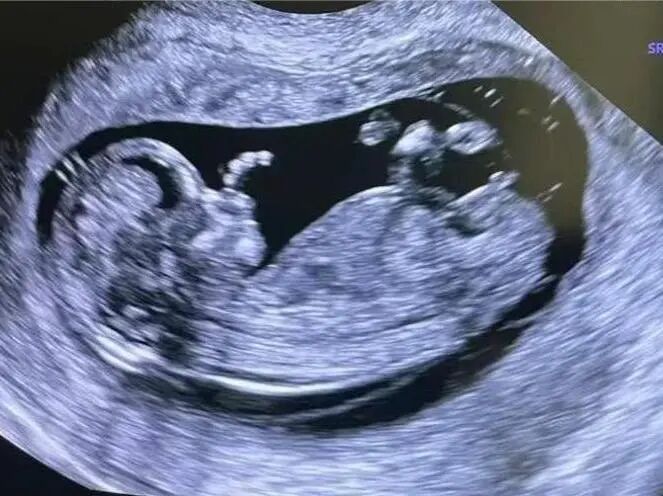

1月7日,贵州航天医院第91次晨读会由我院超声科医师杨向蓉作学术交流,她以“小微泡,大作用——右心声学造影”为题,详细讲解了右心声学造影的基本原理、适用情况、操作方式及心脏异常分流评估特点等内容,涵盖了该技术的实施条件、所用造影剂类型及多种激发试验方法,并通过多个病例图文资料分享了右心声学造影在相关症状病因探寻中的辅助角色,为临床评估提供了一种观察途径,有助于从循环角度了解某些症状的可能原因,在相应症状的病因分析中具有一定的参考意义。 贵州航天医院 超声科专家简介 吴艳辉 中共党员,超声科学科带头人,主任医师 专业擅长:从事超声诊断工作30余年,对心血管、小器官超声、超声引导下介入等具有丰富的临床经验。 胡大海 超声科主任,副主任医师 专业擅长:从事超声工作20余年,对心血管、外周血管、浅表器官、成人颅脑、超声造影诊断及超声引导下介入等具有丰富的临床经验。 骆科美 中共党员,超声科副主任医师 专业擅长:从事超声诊断工作30余年,对胎儿心脏及颅脑、妇产超声诊断、盆底超声等具有丰富的临床经验。 刘 敏 超声科副主任医师 专业擅长:从事超声诊断工作20余年,对妇产科超声、心脏血管超声诊断具有丰富的临床经验。 韩锡铁 超声科副主任医师 专业擅长:从事超声诊断近20年,对心血管、外周血管、浅表器官、肌骨神经超声诊断具有丰富的临床经验。 杨向蓉 中共党员,超声科主治医师 专业擅长:从事超声诊断工作16年,擅长心血管、浅表器官、盆底、腹直肌超声、右心声学造影及超声引导介入等技术。 贵州航天医院超声科简介 基本情况 贵州航天医院超声科配备多种超声检查设备(飞利浦彩超(IU-22、IU-Elite、EPIQ5、EPIQ7),迈瑞彩色超声(ResonaI9T、RechoR9、Resona I9、DC-8)、GE-VolusonE8、汕头SIUIAPogee6800、床旁彩色超声诊断仪等),设有心血管诊室、外周血管诊室、妇产科诊室、腹部诊室、绿色通道、浅表小器官等检查室。 诊疗范围 科室业务覆盖腹部、泌尿、妇科、产科(常规、NT筛查、系统筛查及高危妊娠监护)、成人心脏、外周血管、浅表器官(包含甲状腺、乳腺、阴囊、眼睛等)、颅脑(小儿颅脑、成人帕金森辅助筛查)、小儿肺超、超声造影、盆底、腹直肌、肌骨神经等检查及各种超声介入引导。 专科特色 四肢血管超声检查、产前系统筛查及超声监护、超声造影检查技术、介入超声临床应用、经颅脑实质超声辅助筛查诊断帕金森病、小儿髋关节筛查、女性性早熟超声诊断、盆底、腹直肌超声检查等。 NT超声检查 超声介入引导 肝脏超声造影 甲状腺造影 颅脑超声帕金森辅助检查 乳腺超声造影 上肢动静脉造瘘超声检查 双胎超声筛查 下肢血管超声检查 右心造影 end